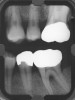

Figure 1a  Long-term results of a case involving a 55-year-old woman treated by regenerative periodontal surgery followed by periodontal maintenance every 3 months for 8 years. (A) Radiograph taken in May 2000

Figure 1a

Figure 1b  Long-term results of a case involving a 55-year-old woman treated by regenerative periodontal surgery followed by periodontal maintenance every 3 months for 8 years. (B) radiograph of the same area taken in July 2008.</a></span><P>Figure 1b</P></div>    <div class=